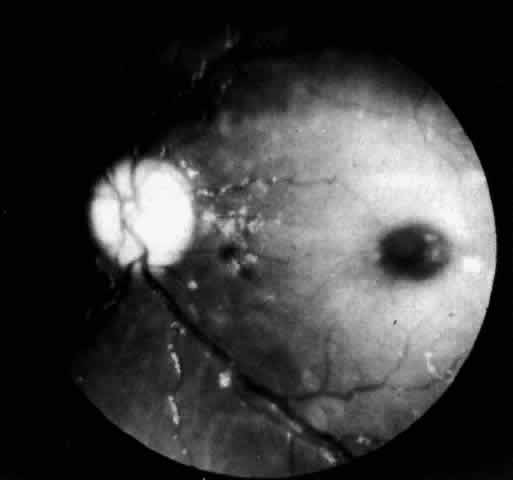

A more widespread opacification of the retina can occur due to involvement of the ganglion cells in the posterior pole. This was observed by Wray4 in a 3½-year-old child with Tay-Sachs disease. The child had black hair and brown eyes, and the cherry-red spot at the macula was brown. The patient was blind, with marked optic atrophy (Fig. 4).

|

A dynamic process of development of the macular cherry-red spot occurs paralleling the infant's progressive neurologic disorder. The cherry-red spot can be observed as early as 2 months of age and is conspicuous at age 4 to 6 months. Loss of visual acuity may occur without noticeable change in the circular halo. But, in time, the ganglion cells atrophy and optic atrophy and loss of the nerve fiber layer occurs. At this stage blindness coincides.